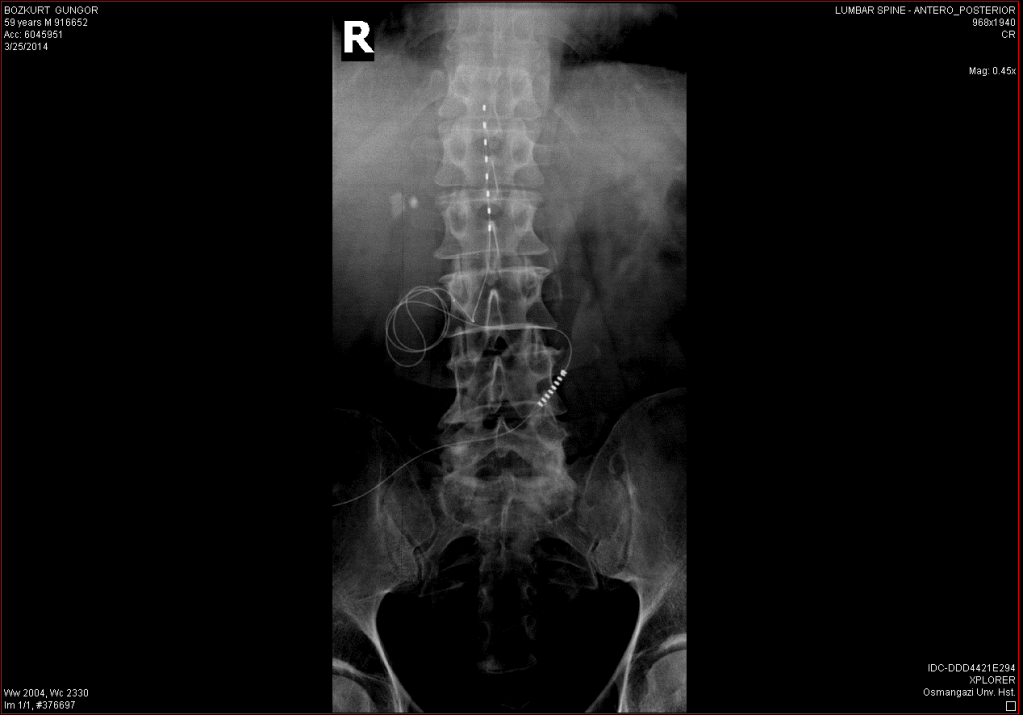

Söz konusu yöntemlerin ağrıları geçirebilecek mucizevi yöntemler olup olmadığını kaydeden Prof. Dr. Güleç, hastaların büyük çoğunluğuna yaşam kalitelerini önemli ölçüde artıracak müdahalelerde bulunabildiklerini belirterek ağrı pili (spinal kord stimülasyonu) uygulamasını anlattı. “Ağrı pili diye adlandırdığımız bu uygulamada bel, göğüs ya da boyun bölgesinde omuriliğin arka kısmına elektriksel uyarılar vererek ağrı iletiminin durdurulması amaçlanır. Ağrı pili; ilaçlar, fizik tedavi uygulamaları, basit girişimsel yöntemler ve cerrahi ile geçirilemeyen ya da bu yöntemlerle geçmeyeceği bilinen ağrıların tedavisi için kullanılır. Bunların dışında kontrol edilemeyen kalp ağrıları, kollar ve bacaklarda damar tıkanıklığı nedeniyle olan ağrının tedavisi ve kanlanmayı artırarak kangrene gidişi engellemek amacıyla da kullanılır. Öncelikle bu hastalar bu tedaviden fayda görebilirler mi diye değerlendirilir. Uygun olduğu düşünülen hastalar başka bölümlerin de görüşünü almak amacıyla Beyin Cerrahisi, Fizik Tedavi ve Psikiyatri Bölümlerine konsülte edilir. Tüm bölümler uygun gördükten sonra pil takılmak üzere hasta hazırlanır. Ameliyathanede yapılan işlem sırasında hasta genel anestezi almaz. Hastaya ağrı kesici ve sakinleştirici ilaçlar verildikten sonra lokal anestezi uygulanır. Bir iğne ile omuriliğin arkasındaki bir alan olan epidural mesafeye girilir. İğne içinden elektriksel uyarıları verecek olan ‘lead’ olarak adlandırdığımız ince bir kabloya benzeyen tel geçirilerek uygun yere yerleştirilir. Doğru yeri anlamak için bu telden uyarı vererek hastaya nerede akım hissettiği sorulur ve sonrasında lead en uygun yere yerleştirilir. Deneme aşaması için bu telin diğer ucu ciltten dışarı çıkartılarak cep telefonu benzeri bir cihaza bağlanır. Cihaz teknik elemanlar tarafından ağrıyı giderecek en doğru akımı vermek üzere ayarlanır. Bir iki haftalık deneme aşaması sonrasında ağrıları rahatlayan hastalar (yaklaşık %70) tekrar ameliyathaneye alınır, hastanın vücuduna kibrit kutusu büyüklüğündeki kalıcı pil yerleştirilir. Yeni pillerin ömürleri 10 yıla ulaşmıştır. Biten piller küçük bir cerrahi girişim yapılarak yenisiyle değiştirilir.”